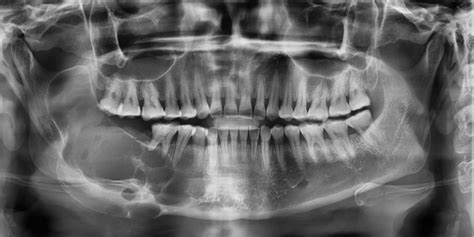

Radiografía que muestra un quiste maxilar como una zona oscura.

El diagnóstico de los quistes maxilares generalmente se realiza mediante una combinación de exámenes físicos, estudios de imágenes y evaluaciones clínicas. El principal método para detectar un quiste maxilar es a través de una radiografía, en la que se puede observar una mancha de color oscuro en el hueso. En la ortopantomografía (radiografía en 2D de toda la boca) el quiste maxilar se observa como una zona oscura y redondeada en forma de bolsa.